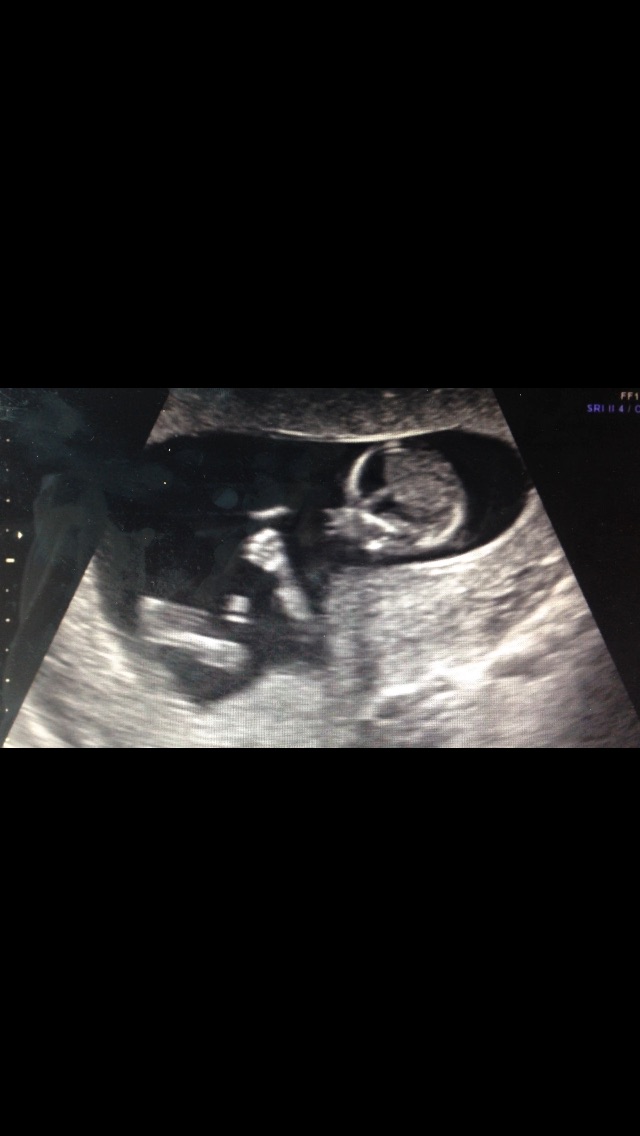

This is pretty interesting! According to this theory, a girl will have a more rounded forehead and a boy will have more of a slope forehead. This is my sonogram at 14 weeks. And the skull looks to be more sloped straight down then rounded and bulb like... but it's still too early to tell. What do you ladies think? And has anyone else ever looked into it?

when pregnant with my other kids, and have said "the profile just looks like a ___(insert boy/girl here____!" So this theory excites me and could definitely be plausible. I should dig out the albums and look to see if it holds true to my kids.